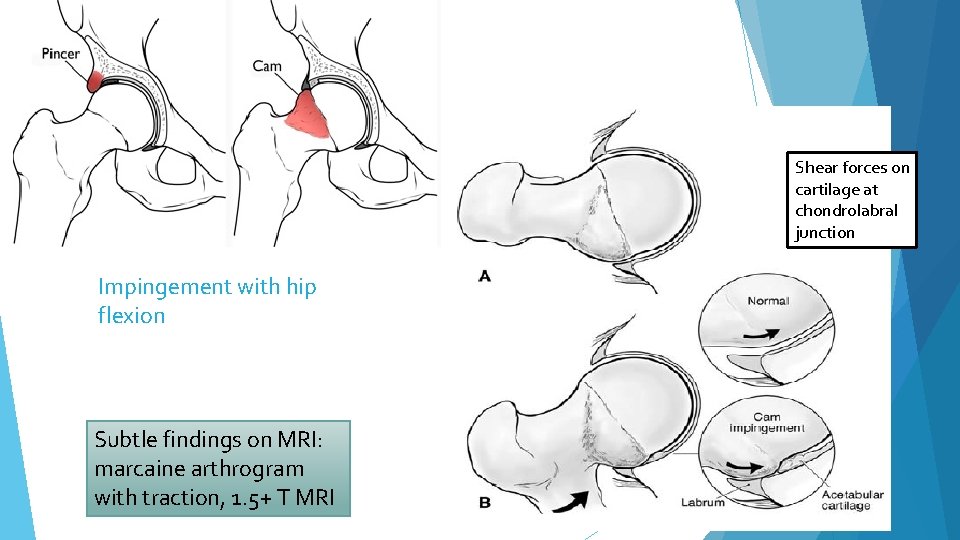

Shear forces on cartilage at chondrolabral junction Impingement with hip flexion Subtle findings on MRI: marcaine arthrogram with traction, 1. 5+ T MRI